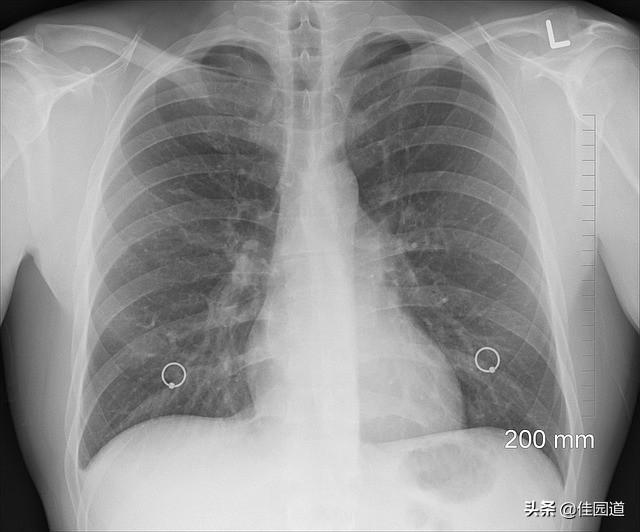

À l'école, nos professeurs nous ont répété à maintes reprises que la maladie ne se développe pas selon les manuels scolaires ! Les patients infectés par une nouvelle pneumonie à coronavirus ne présentent pas tous des symptômes typiques, ce qui complique la tâche des médecins lorsqu'il s'agit de poser un diagnostic. Mais ne vous inquiétez pas, nous serons également très prudents dans le diagnostic du nouveau coronavirus. Nous devons prendre en considération l'épidémiologie (par exemple, les antécédents de résidence à Wuhan, Hubei, les contacts avec des personnes venant de Wuhan, etc.), les symptômes cliniques (fièvre, toux, malaise, etc.) et les tests auxiliaires pertinents (tests sanguins de routine, radiographie des poumons, etc. S'il existe un degré élevé de suspicion que la pneumonie à nouveau coronavirus peut être la cause de la maladie, nous devrons discuter avec des experts, et enfin, nous devrons confirmer le diagnostic à l'aide d'échantillons respiratoires. Pour confirmer le diagnostic, les échantillons respiratoires ou sanguins doivent être positifs pour l'acide nucléique du nouveau coronavirus par RT-PCR en fluorescence en temps réel. Si le cas suspect présente deux tests consécutifs négatifs pour l'acide nucléique d'agents pathogènes respiratoires (au moins un jour entre les échantillons), il peut être exclu.

Selon le protocole de prise en charge de la pneumonie à nouveau coronavirus, les principales manifestations de la pneumonie à nouveau coronavirus sont la fièvre, la toux sèche, le malaise et, chez quelques patients, la congestion nasale, l'écoulement nasal, les maux de gorge et la diarrhée. Les symptômes les plus fréquents chez les patients infectés par un nouveau coronavirus sont la fièvre et les malaises, comme le mentionnent deux articles récemment publiés. Les données de 41 cas d'infection confirmée ont montré que presque tous les patients (98 %) de la population confirmée avaient de la fièvre, 76 % toussaient et 44 % souffraient de myalgie/fatigue. Une analyse de 99 cas a montré que 83 % d'entre eux avaient de la fièvre, 82 % de la toux, 31 % de l'essoufflement et quelques-uns des maux de tête, des maux de gorge, des écoulements nasaux, des douleurs thoraciques et de la diarrhée, au moins un des symptômes ci-dessus étant présent dans plus de 90 % des cas. La lymphopénie était fréquente dans la numération sanguine, et la tomodensitométrie thoracique a révélé chez tous les patients d'importantes anomalies pulmonaires, notamment une opacité en verre dépoli, l'accumulation de plusieurs segments pulmonaires ou de plusieurs lobes. Toutefois, il est également vrai que certains patients atteints d'une nouvelle infection à coronavirus n'ont pas de fièvre et ont une température normale, mais il s'agit après tout d'une minorité.

Les radiographies du thorax montrent de multiples petites taches au début de la maladie, puis la maladie évolue pour montrer de multiples taches infiltrantes et de multiples taches de verre dépoli dans les deux poumons, et les patients sévères peuvent montrer de graves changements solides dans les deux poumons, se manifestant par les poumons blancs familiers.

Le diagnostic définitif nécessite un test d'acide nucléique du nouveau coronavirus ou le séquençage du gène viral.